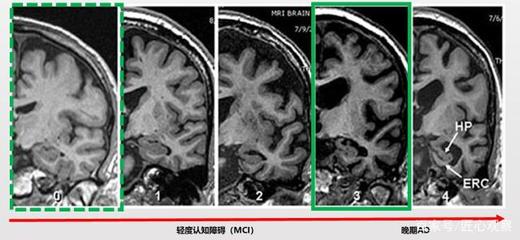

3. 诊断与监测设备:高分辨率MRI、便携式脑血氧监测仪等创新产品,为早期诊断和长期监护提供了支持。部分设备结合人工智能算法,能够自动分析脑电信号或影像数据,提高诊断效率。